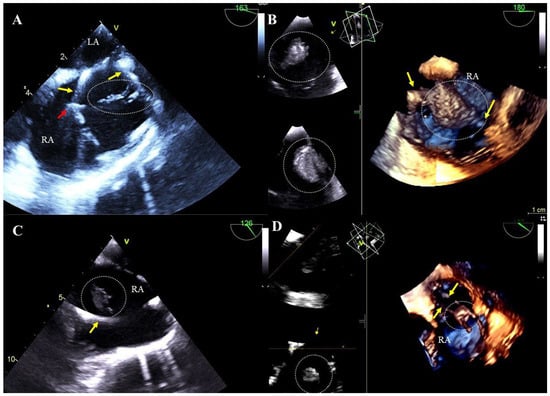

Floating scar tissue attached to the lead: small, hyperechoic structures with uneven contours, more rigid and less mobile than clots of uniform echogenicity being components of scar tissue developed in response to lead presence. They probably arise from progressive fibrosis of non-lysed blood clots (Figure 1A, Movie S1).

Blood clots on the leads: most often airy, hypoechoic, flaccid, flag-like formations, sometimes large and hyperechoic with a smooth surface (Figure 1B, Movie S2).

Vegetation-like masses: well-saturated formations resembling vegetations in shape and mobility, associated with leads and recorded in patients without symptoms of infection. They are probably a residue of past infections (old fibrosed vegetations). It cannot be ruled out that these masses are unusual-looking old clots or adhesions (Figure 1C,D, Movie S3).

Figure 1. TEE (2D, 3D) before TLE showing additional structures on the leads. Mobile structures correspond to scar tissue on the atrial lead (dashed line) (A). The mass on the lead corresponds to a large thrombus visualized in the right atrium (B). In the right atrium, in the patient with no signs of infection, an additional structure on the lead was visualized, which may correspond to a veg-like structure (C). In the right atrium, in the patient with no signs of infection, an additional structure was binding two leads; this may represent scar tissue or a veg-like structure (D). (Yellow arrows mark the electrodes, and additional structures are displayed in circles.).